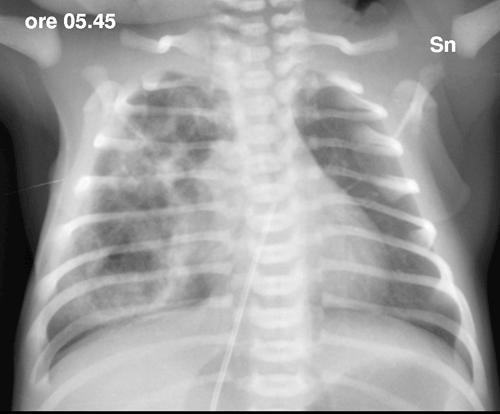

Una radiografia del torace documenta un campo polmonare di destra in gran parte occupato da opacit� disomogenea, nel cui contesto si evidenziano multiple areole di radio-trasparenza; campo sinistro senza alterazioni e lieve sbandieramento del mediastino (Figura 1). Il quadro appare compatibile con la diagnosi prenatale di CCAM. Visto il rapido miglioramento clinico del quadro respiratorio e la normalit� dell'emogas-analisi, la N-CPAP viene rimossa dopo poche ore. | Figura 1. Rx-torace: campo polmonare di dx in gran parte occupato da opacit� disomogenea: si

evidenziano multiple areole di radio-trasparenza; campo sx senza

alterazioni e lieve sbandieramento del mediastino. L'esame

evidenzia un catetere ombelicale che si proietta in sede atriale

(ritirato subito dopo). In sede epigastrica un area circolare di

radiotrasparenza, attribuibile a un elemento dell'incubatore. Per una miglior definizione del problema, anche in vista dell'intervento, viene effettuata una TC-polmonare che evidenzia a destra una formazione irregolarmente ovalare di circa 5 cm di diametro massimo, apparentemente ben marginata, con numerose formazioni cistiche aerate circostanti (Figure 2 e Figura 3). Alla luce della diagnosi il bambino viene quindi sottoposto con successo ad intervento di lobectomia parziale dei lobi medio e superiore di destra. |